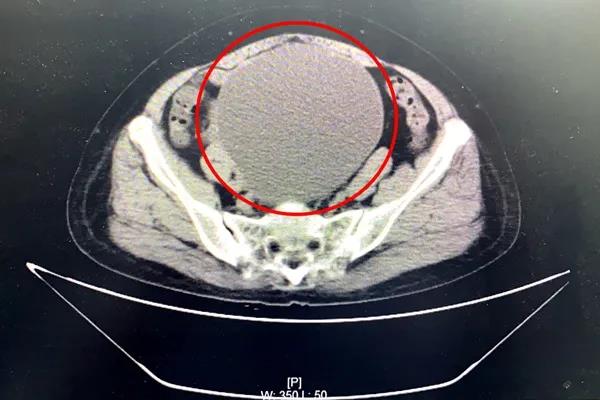

7月13日,63岁的陆阿姨来到我院外科门诊就诊。她自觉6月开始腹部增大明显,并感腹部坠胀不适感。外科检查全腹部CT提示:盆腔内巨大囊性病灶,考虑浆液性囊腺瘤,近20公分大!患者及家属对病情十分担忧。

妇产科顾爱玲主任前来会诊。经检查,患者腹部包块增大明显,盆腔巨大包块已如怀孕近6月大小。顾主任详细问询病史、查体,并再次至放射科与医生共同阅片,考虑患者巨大盆腔肿物瘤良性可能大。她与患者及家属详细沟通了相关病情,逐渐打消了患者及家属顾虑。患者及家属决定留我院进一步诊治。

一般来讲,盆腔巨大肿物,直径达20cm,手术方式会倾向选择开腹手术。但是考虑到患者曾有过2次腹部手术史,一次为17年前因“子宫肌瘤”在外院行经腹全子宫切除术,一次为阑尾切除手术,又盆腔粘连严重,且开腹手术伤口长、恢复慢,会给患者增加痛苦。

顾爱玲主任经反复权衡考虑,结合患者各项检查,决定克服困难,坚持微创理念,尝试创新为患者行腹腔镜下微创手术——腹腔镜下盆腔巨大包块切除手术。顾爱玲主任表示:“我们会在术中使用一次性微小切口保护套及自制手套完成密闭气腹腔,而且可以在直视下取出肿瘤,类似腹腔镜下无气腹腹腔镜手术,手术更便捷、更安全。”

7月16日,顾爱玲主任与朱红燕主治医师合作,顺利为患者完成腹腔镜下巨大卵巢囊肿切除、双侧附件切除术、盆腔粘连分解术。手术很顺利,出血少,伤口小,腹部伤口疼痛不明显,术后第一天患者就能下床行走了,并且没有出现并发症。术后肿瘤病理也确认为良性。